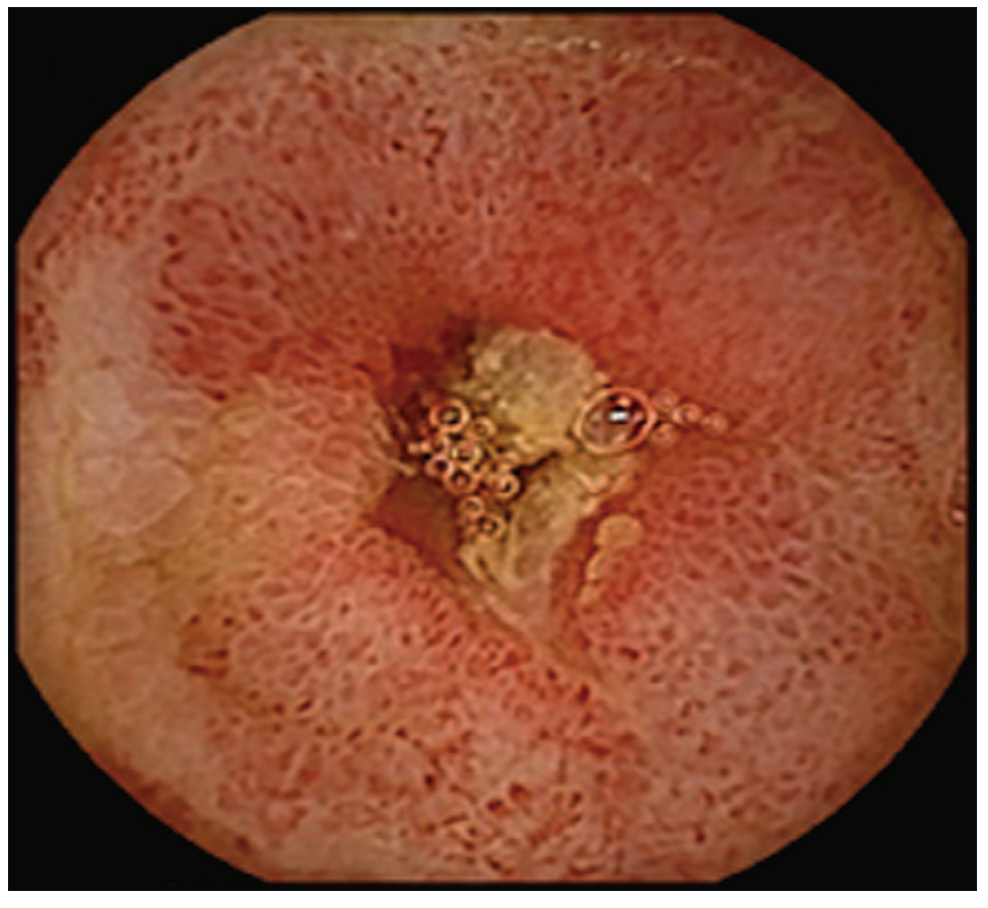

Con respecto a las imágenes, la radiografía directa de abdomen y la telerradiografía de tórax fueron normales. Se realizó una tomografía computada (TC) de abdomen que mostró asas de intestino delgado de paredes engrosadas sin estenosis, ausencia de líquido libre y presencia de divertículos en el colon. Se administraron hidratación y alimentación parenterales, y dos transfusiones de sangre. Se solicitó una videoendoscopía digestiva alta que evidenció gastropatía antral. En la videocolonoscopía hasta ciego se observó diverticulosis sigmoidea. Se constató la presencia de sangre fresca a través de la válvula íleocecal pero no se logró canular el íleon. Se solicitó una cápsula endoscópica (CE) donde se observó la presencia de sangre fresca y coágulos desde el yeyuno medio hasta íleon, con múltiples úlceras lineales, cicatrices y vasos de neo formación que alternaban con mucosa de aspecto normal (Figuras 1-3).

Figura 1. Úlceras. Disminución del calibre

Las zonas afectadas presentaban disminución del calibre de la luz intestinal. Dichos hallazgos eran compatibles con enfermedad de Crohn. No se observó el pasaje de la cápsula a colon a través de la válvula íleo cecal.